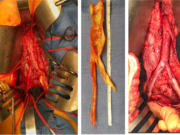

Enduring PROMISE: Real-world outcomes study suggests results continue to flow from transcatheter arterialization of...

First retrospective analysis shows comparable outcomes data to those found in PROMISE II pivotal trial, authors report.

The first post-approval multicenter analysis of so-called “no-option”...